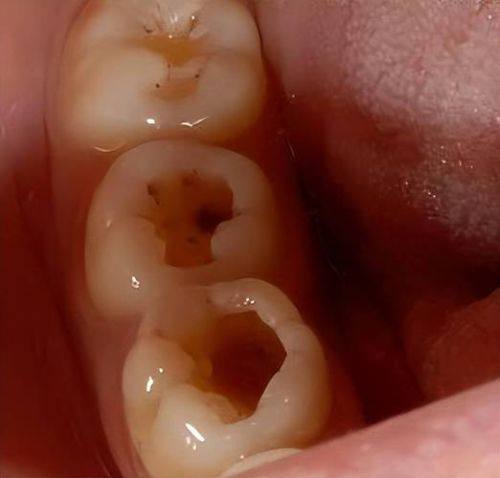

对于一些生活在低消费地区,并且龋齿病情比较轻的朋友来说,修复龋齿的费用会相对低一些。在这些地区,物价水平本身就不高,医疗成本也相对较低。而且病情轻意味着治疗过程相对简单,医生通常会使用玻璃离子或复合树脂等材料对龋齿局部进行填充。这种填充治疗方式比较常见,费用大概在200元到300元一颗。比如说,在一些三四线城市或者县城,当地的消费水平不高,如果你的龋齿只是刚开始出现,没有伤到牙神经,那么选择这种填充治疗,花费就不会太多。这对于特别多患者来说,是一种经济实惠的治疗选择。

要是你所在的地区是高消费地区,或者龋齿病情比较重,那么修复龋齿的费用就会高一些。在高消费地区,像一线城市,物价和医疗成本都比较高,这就会导致治疗费用相应增加。而当龋齿病情较重时,可能不仅仅是补牙那么简单了。比如龋齿已经伤到了牙神经,在进行补牙以后,可能还需要安装牙冠来保护牙齿。安装牙冠的费用会比单纯补牙高特别多,所以总体费用大概在500元到800元一颗。例如在上海、北京这样的大城市,如果你的龋齿比较重度,医生可能会建议你精良行根管治疗,然后再安装牙冠,这样一套下来费用就会相对较高。